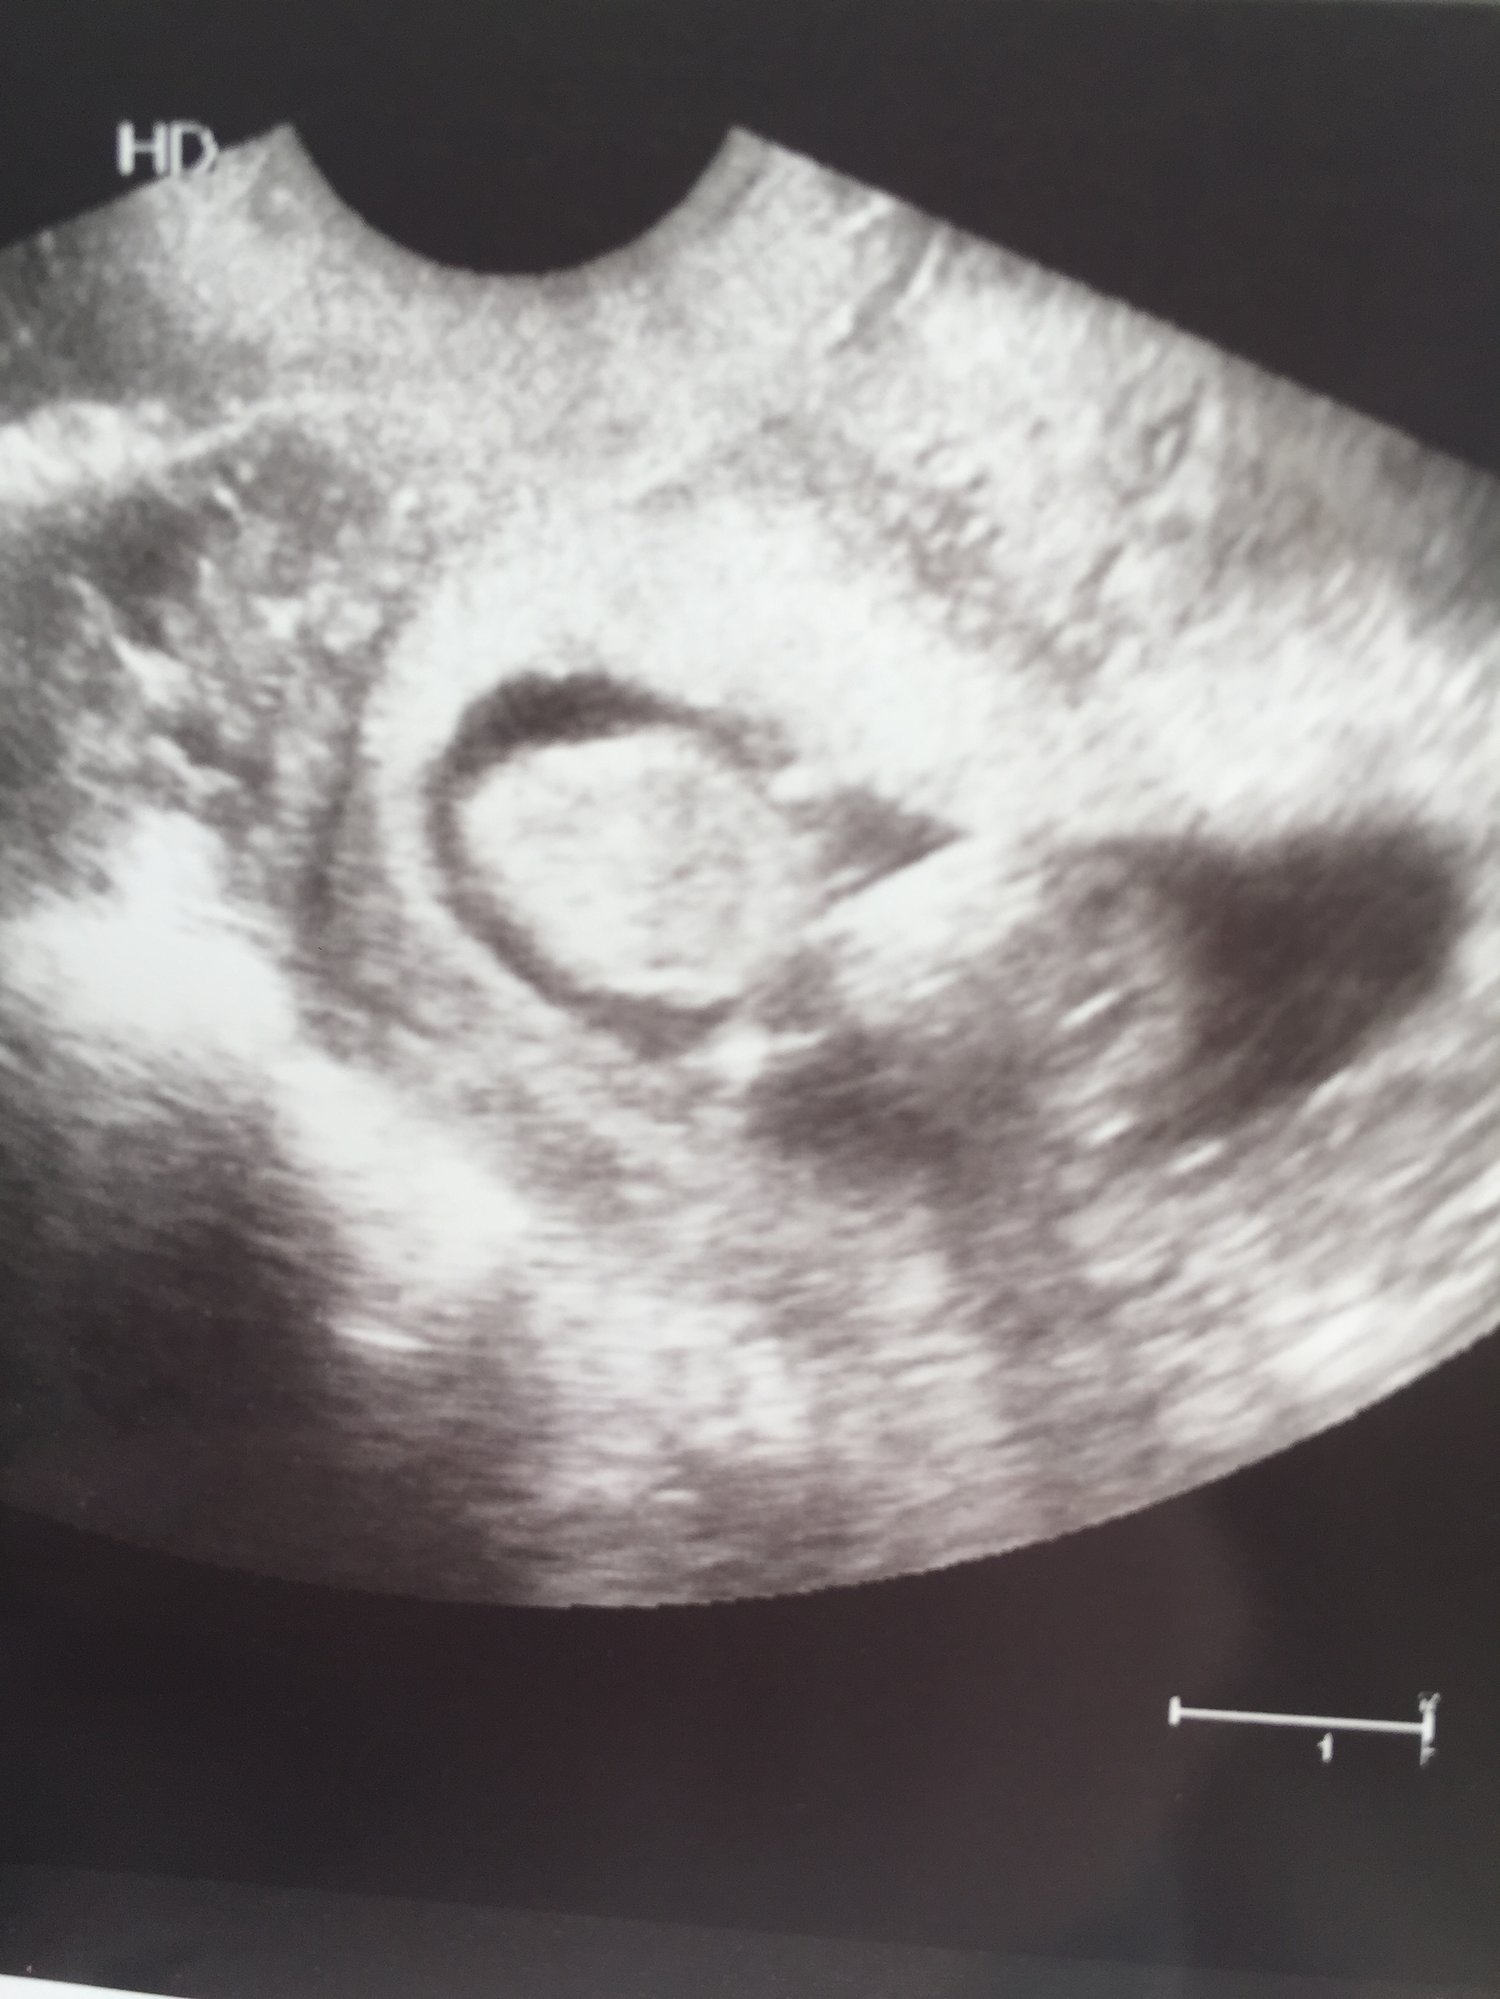

Lmp says I'm 10 weeks 2 days! Waiting to see what my midwife says it actually is

First appt with our midwife. 10w2d. Tracking exactly where we thought we were. When the image came up our three year old said, "it's a baby!"